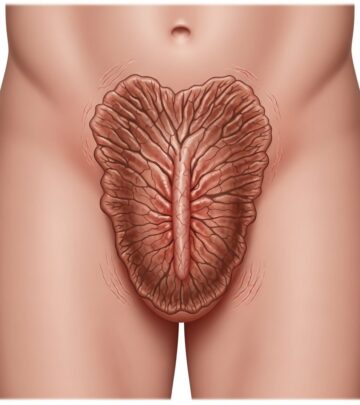

Treatment of Gastric Varices

Gastric varices present unique management challenges as they are often larger than esophageal varices, more difficult to access endoscopically, and carry higher rebleeding rates. Cyanoacrylate injection (tissue adhesive) has become the preferred endoscopic approach for gastric varices, though special expertise is required for safe application. TIPS may be considered earlier in the management of gastric variceal bleeding compared to esophageal varices due to the less satisfactory results with endoscopic therapy alone.